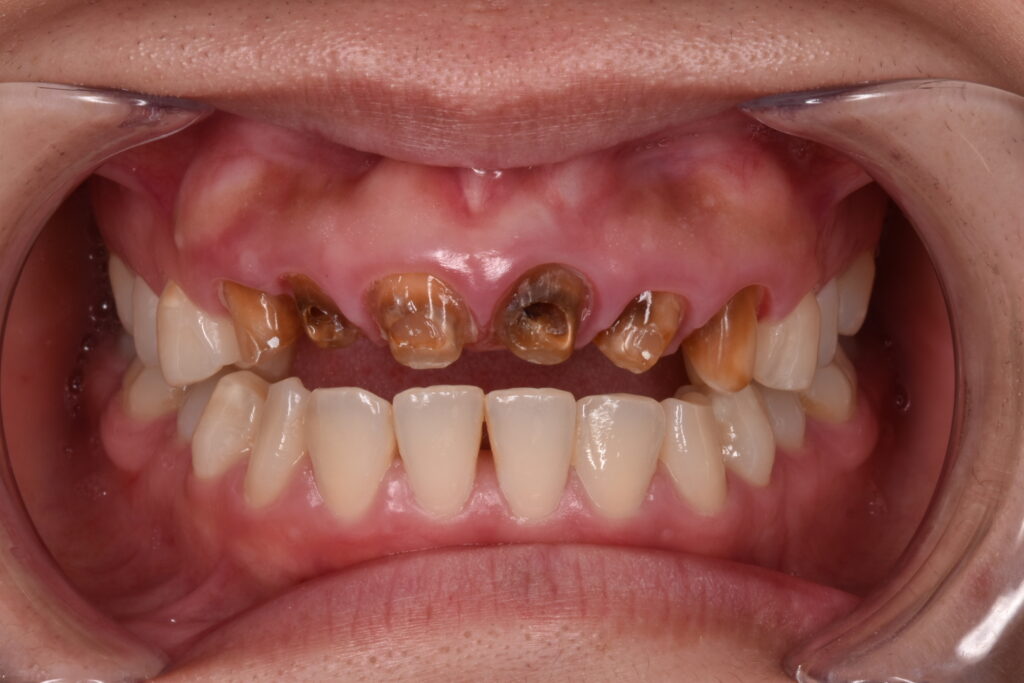

初診時の状態

白い6連結のセラミックがありますが、右側のセラミックの前歯は破折しています。(写真左)また6連結の中央でジルコニアのフレームごと破折していることも確認できます。(写真中央)左の前歯は神経処置がされておらず穴だけ開いた状態でした。(神経治療途中?)土台6本全てが茶色から黒色に変色している事が周囲の天然歯と比べてもわかります。

穴だけ開いた歯の状態

神経処置が未処置のまま放置?の歯です。実は下のCTの写真でわかる様に歯の変形があります。ご本人様にお伺いしたところ昔前歯を強打した経験があるとの事でしたが、当時は受診せず経過を診ていたそうです。セラミック治療した歯科ではこの変形した歯について何も伝えられなかったと。。。

ここからは私の推測ですが、、、神経の管の中にビタペックス(消毒効果のある根管充填材)の様なものが確認出来ました。神経治療をトライしてレッジを作ってしまい治療できなかったのでビタペックスを根充材として入れてレジンで蓋をしたのだろうと思います。